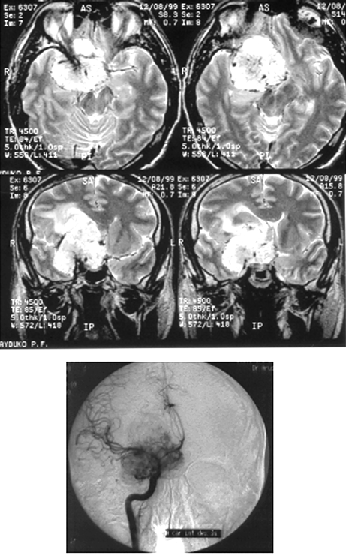

Менингиомы медиальных отделов крыльев основной кости (переднего наклоненного отростка) часто обрастают внутреннюю сонную артерию (рис. 8), внедряются в канал зрительного нерва, распространяются на диафрагму турецкого седла. Удаление их представляет сложную задачу, в отдельных случаях радикальное удаление таких опухолей неосуществимо. Применение системы интраоперационной нейронавигации позволяет локализовать включенную в опухоль внутреннююю сонную артерию и снижает риск ее ранения.

Рисунок 8. Менингиома медиальных отделов крыльев основной кости (вверху — МРТ, Т2-взвешенные изображения; внизу — правосторонняя селективная каротидная АГ, артериальная фаза. Стрелкой показано сужение просвета внутренней сонной артерии)

Гиперостотические инфильтративные менингиомы крыльев основной кости представлены, как правило, гиперостозом крыла основной кости различной степени выраженности и мягкотканными компонентами по обе стороны от гиперостоза (рис. 9).

Рисунок 9. Гиперостотическая менингиома крыльев основной кости справа с формированием мягкотканного компонента в глазнице, средней черепной и подвисочной ямках. КТ (вверху) и МРТ (внизу), с контрастным усилением)